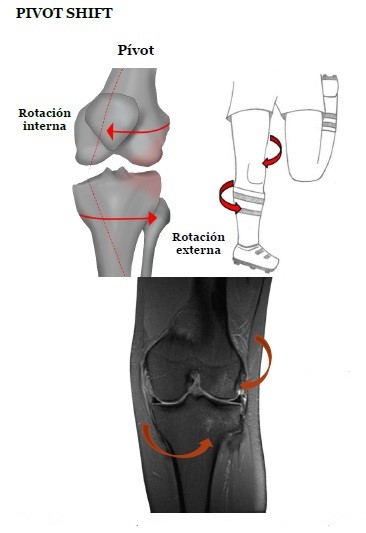

Pivot shift

Es una contusión ósea del labio posterior de la meseta tibial medial. Ocurre durante la reducción de rodilla después de una lesión de cambio de pivote y está altamente asociada con desgarros del LCA y desgarro periférico o separación meniscocapsular del menisco medial posterior del asta. Este patrón se observa en casos de lesiones de la cápsula anterior de la rodilla, se caracteriza por una aparente subluxación de la tibia cuando la rodilla se flexiona y extiende.

Patrones de edema óseo:

- Meseta tibial posterolateral y parte media del cóndilo femoral lateral.

Lesiones de partes blandas:

- Desgarros del ligamento cruzado anterior (LCA).

El traumatismo de la rodilla en valgo, asociado a flexión y rotación externa de la tibia, es considerado como el tipo de presentación más frecuente dentro de las lesiones en valgo. Incluso se ha descrito como el mecanismo traumático más común de las lesiones complejas de rodilla, representando alrededor del 46%.

Este tipo de lesiones se presentan de manera usual en situaciones de rápida desaceleración o cambios súbitos de dirección, por lo que comúnmente se observa en jugadores de fútbol o esquiadores, entre otros. Este tipo de maniobras origina una sobrecarga sobre el ligamento cruzado anterior, que puede dar como resultado su rotura; como consecuencia, se produce una subluxación anterolateral de la tibia, y luego, una impactación del cóndilo femoral lateral con la vertiente posterolateral del platillo tibial. De esta situación podemos encontrar los siguientes hallazgos:[xxv]

- Contusiones en la porción media y/o posterior del cóndilo femoral externo y esquina tibial posterolateral por impactación.

- Contusiones en el cóndilo femoral interno y esquina tibial posteromedial por contragolpe, tras la resolución de la fuerza en valgo.

- Rotura del ligamento colateral medial y ligamento cruzado anterior.

- Mayor riesgo de lesión del menisco interno o externo. De manera ocasional, desgarro de la cápsula posterior y ligamento arcuato/poplíteo.

Ante la presencia de este patrón de edema óseo, es importante valorar la integridad del LCA, teniendo en cuenta que, por su localización y trayecto desde el cóndilo femoral lateral en la escotadura intercondílea hasta su inserción distal en la espina tibial anterior, se visualiza mejor en un plano sagital oblicuo, pero nunca olvidar que se debe valorar también en los planos axial y coronal.[xxvi]